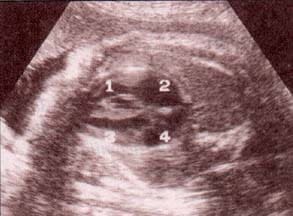

| fig 29.– (a). corazón corte 4 cámaras. proyección apical. 32 semanas. ventrículo izquierdo (1). ventrículo derecho (2). aurícula izquierda (3). aurícula derecha (4). | fig. 29. – (b). proyección subcostal. 36 semanas. ventrículo izquierdo (1). ventrículo derecho (2). aurícula izquierda (3). aurícula derecha (4). |